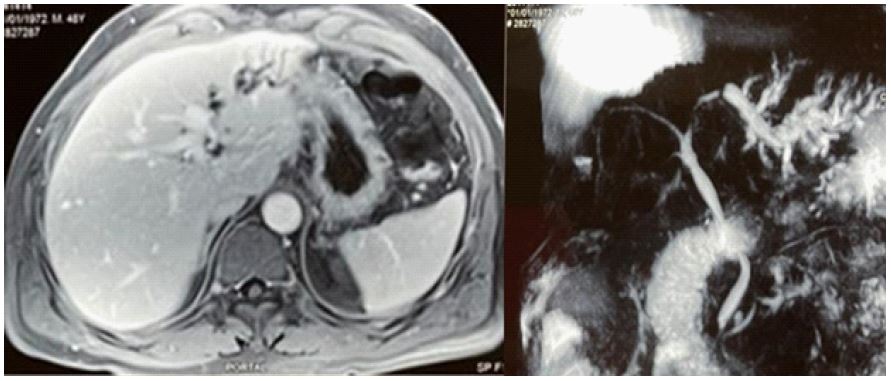

Subsequent abdominal MRI with MRCP, obtained for evaluation of suspected acute gallstone pancreatitis, revealed dilatation of the left hepatic lobe biliary system. A 9 mm filling defect with associated ductal narrowing was identified in the proximal left hepatic duct near the confluence, highly suggestive of an impacted calculus. The upstream left hepatic duct was dilated to 8 mm. Additional segmental filling defects were noted in the segment III duct along with peripheral biliary sludge deposits. The remainder of the biliary tree and hepatic parenchyma was normal, with a normal 8 mm common bile duct demonstrating appropriate distal tapering and no evidence of filling defects (Figure 1).

Figure 1: Left panel shows abdominal MRI (T1-weighted sequence) demonstrating dilatation of the left intrahepatic bile duct. Right panel displays MRCP revealing multiple segmental duct dilatations in segments II and III.